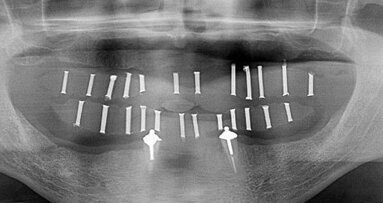

Als Preisträger diverser Awards und Gastredner an über 150 internationalen Konferenzen freuen wir uns natürlich sehr darüber, Prof. Dr. Paulo Malo begrüßen zu dürfen. Das MALO CLINIC Protokoll hat die Oralchirurgie, insbesondere hinsichtlich der Implantologie und festsitzenden Versorgungen, revolutioniert. Hinzu kommt der weltweit führende Kliniker für Parodontologie: Prof. Dr. Dennis P. Tarnow. Als Professor und Direktor des Lehrstuhls für Zahnmedizinische Implantologie am College of Dental Medicine der Columbia University New York und Gewinner des Master Clinician Award der American Academy of Periodontology wird er sich den Themen Ätiologie und Behandlungslösungen über Sofortimplantationen in Extraktionsalveolen widmen – es ist das erste Mal überhaupt, dass Prof. Tarnow in Hamburg zu hören ist. Darauf sind wir natürlich sehr stolz. Der Dritte im Bunde ist mein geschätzter Hamburger Kollege Prof. Dr. Dr. Max Heiland, Direktor der Klinik und Poliklinik für Mund-, Kiefer- und Gesichtschirurgie des Universitätsklinikums Hamburg-Eppendorf.